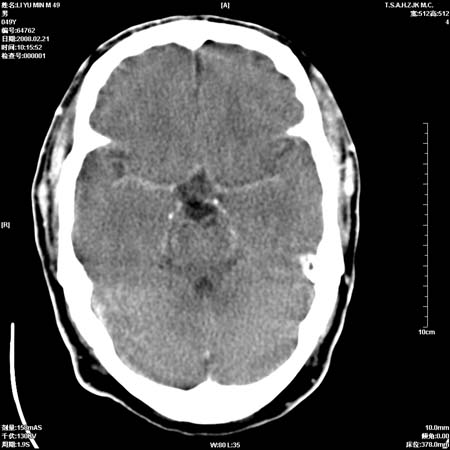

男性, 49岁, 头痛, 行ct检查后, 我科一名大夫报了蛛网膜下腔出血, 请大家讨论!

大脑纵裂池及鞍上池应该有蛛血

支持蛛网膜下腔出血。